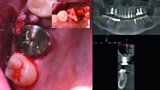

Digital workflow and application of PRF and ozone therapy in oral rehabilitation